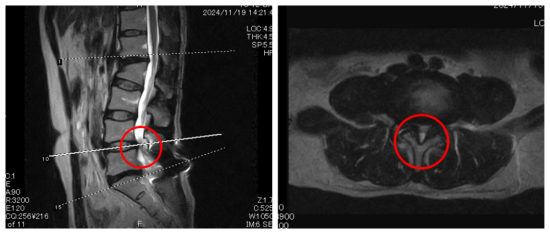

┃検査・診断

赤い丸の部分(L4/5)に強い狭窄を認めました。